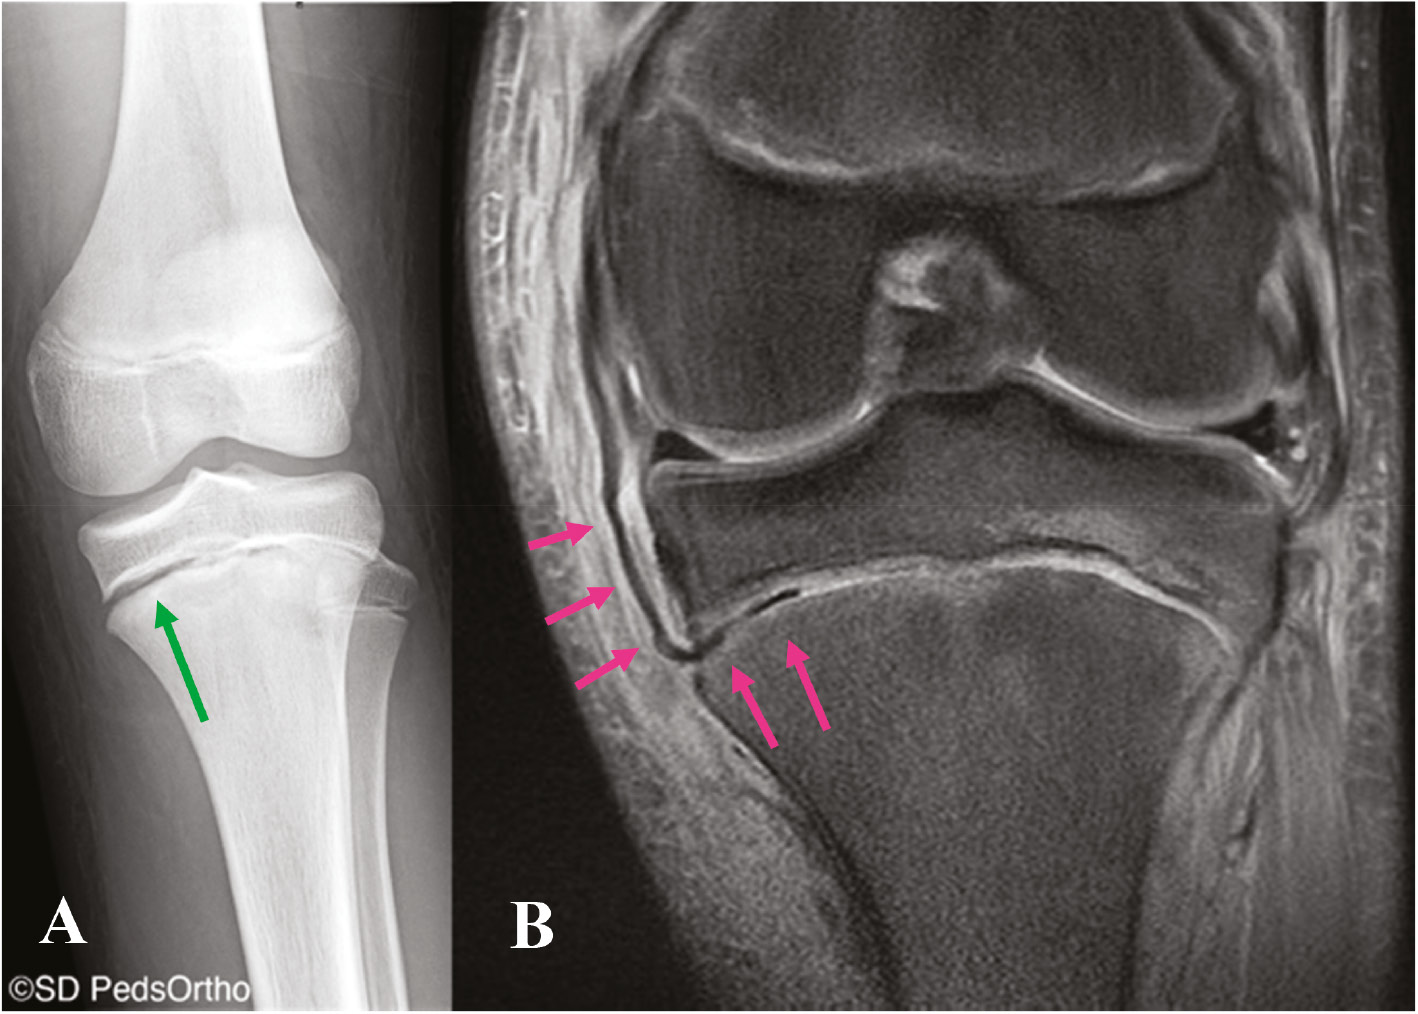

At a minimum, two radiographs (AP/lateral views) of the knee should be obtained, but a four-view series (AP/lateral/merchant/tunnel views) may be preferable to minimize the chance of missing other pathology. Examples would be a Salter-Harris III fracture of the medial femoral condyle, which represents a transitional fracture that is seen in adolescents near skeletal maturity as an alternative to an adult MCL injury (Figure 2). Additional injuries to the MCL complex include medial epicondyle fractures or fractures to the most prominent aspect of the medial condyle, bony avulsions of the deep MCL, which are frequently associated with ACL tears (Figure 3), or even the rare Salter-Harris I or II fracture of the proximal tibia in which the MCL can become interposed within the fracture (Figure 4). With longer-term follow-up, periosteal avulsions of the MCL adjacent to the medial epicondyle may result in the formation of a Pellegrini-Stieda lesion where ossification of the proximal MCL is present from either a previous avulsion of the MCL or ossification within the MCL from a chronic tear/injury pattern (Figure 5). In cases of chronic instability with suspected genu valgum, a long leg alignment film is helpful in quantifying any underlying coronal plane malalignment that may need to be corrected simultaneously or prior to a ligamentous reconstruction.

Figure 4. 12-year-old male with a left knee injury with a Salter-Harris I fracture of the proximal tibia with (A) asymmetric widening of the medial physis (green arrow) with (B) a coronal MRI image demonstrating the distal fibers of the superficial MCL interposed within the fracture (pink arrows).